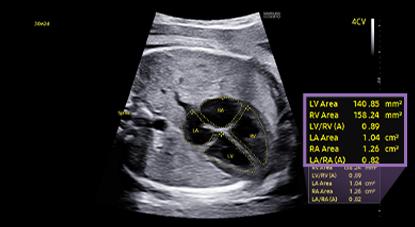

HeartAssist™, a feature based on Deep Learning technology, provides automatic classification of ultrasound image into measurement views required for fetal heart diagnosis and provides measurement results.

MPI+ is able to semi-automatically measure LV MPI and RV MPI, providing a high reproducibility. After acquiring Inflow/Outflow doppler, RV MPI proceeds alignment by utilizing synchronized signals of the heartrate and valve movement.

5D Heart Color™ ¹ The function provides 9 standard planes of the heart by using the fetal STIC data as well as important information about fetal heart development in an easy and accurate way in accordance with the AIUM guideline. In addition, it offers dedicated Preset, Predictive Cursor, Diagnostic Alert, and heart Diastole/Systole timepoints.